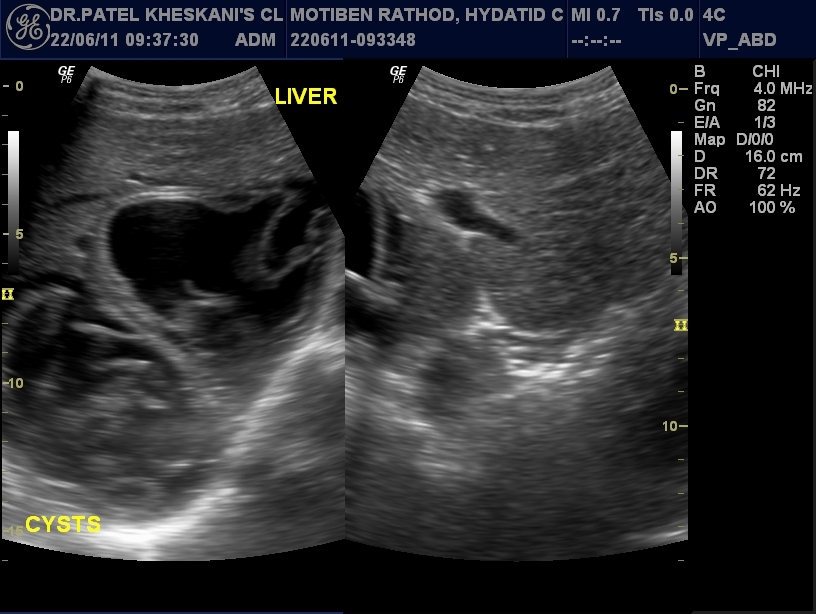

Ultrasonography was done which shows multiple cystic lesions in liver.

One of the crumpled cyst is with multiple septas.